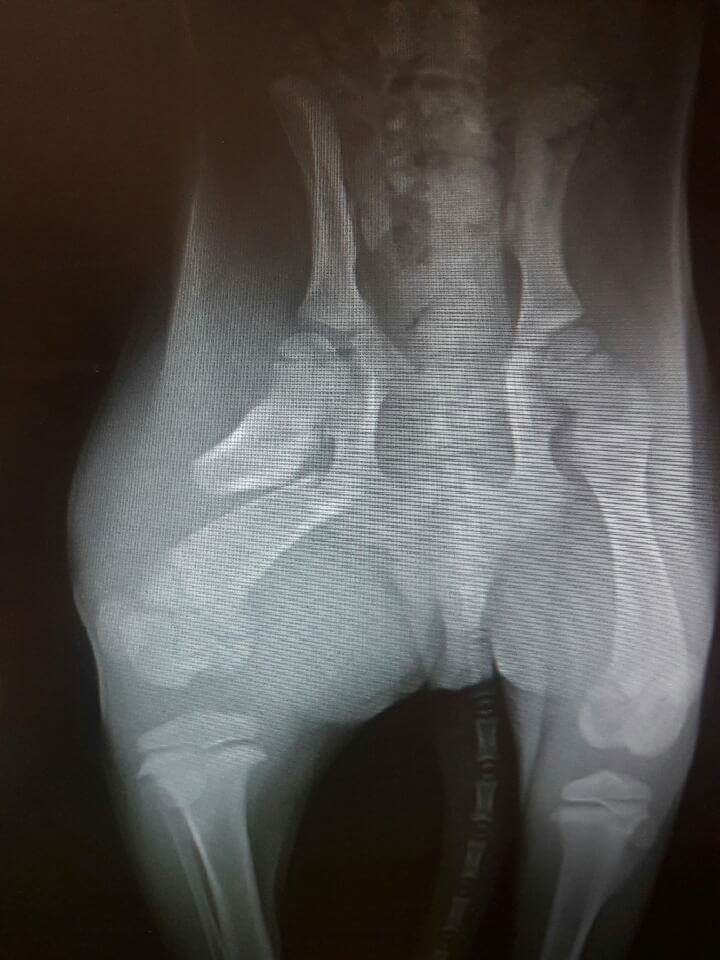

A little husky shep came to Red Lake Rosie's Rescue in late summer with mange and the condition of rickets which is from prenatal and postnatal malnutrition. We named this sweet girl Stella.

Stella was a wonderful puppy that ran around the shelter in spite of her bowed legs, which caused her to trip and fall occasionally. This did not stop this spirited little girl from enjoying life.

Chuckie recovers from rickets

Chuckie was surrendered to Red Lake Rosie's Rescue because his legs were crooked.  Often puppies are surrendered with a condition called "rickets" which often results from prenatal and postnatal malnutrition.  The bones do not develop properly due to mineral deficiencies.  We use nutritional treatment and give time for the legs to straighten and we have never had a case that could not be corrected with our patience and good quality grain free canned and kibble.

Chuckie came in with the condition and was taken by Jean of Carver-Scott Humane Society.  As the photos verify he became a healthy pup and now has a bright future with his new family!

Good morning Karen.  Attached is a new photo of Chuckie. He overcame rickets, and his legs have straightened out and are strong. He turned into a typical mischievous puppy, and his foster family adores him.